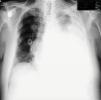

A 62-year-old man was diagnosed with MM (Ig G-kappa), stage IIIA, in June 2010. He was treated with two courses of bortezomib and autologous stem cell transplantation was performed in September 2010. He was given 50mg/day cyclophosphamid as maintenance therapy. In August 2012, he presented with chest pain. A palpable mass in the left hemithorax was detected. X-ray showed multiple rib fractures. PET-CT showed expansive 8×9cm mass located in the left hemithorax in the region of the ninth and tenth ribs (SUV max 15.5). The following were noted in laboratory studies: hemoglobin: 14.1g/dL, white blood cells: 5×109/L, platelets: 242×109/L, creatinine: 0.8mg/dL, uric acid: 6mg/dL, calcium: 10.7mg/dL, total protein: 7.4g/dL, albumin: 4.9g/dL, globulin: 2.5g/dL, kappa: 217mg/dL and β-2 microglobulin: 3668ng/mL. Serum protein electrophoresis was normal, and the 17p13,1 (p53 gene) was negative by FISH. Bone marrow biopsy showed CD138 (+), kappa (+) plasma cell infiltration. The patient was administered lenalidomid–dexamethosone. After two courses, pleural effusion was detected in left hemithorax in November 2012 (Fig. 1). Thoracentesis was performed and revealed exudate with a protein level of 6g/dl. Cytology revealed small lymphocytes, polymorphonuclear leukocytes, mesothelial cells and CD138, IgG and kappa positive atypical plasma cells. HHV-8 was negative in immunohistochemical stain. Bacterial and mycobacterial cultures were negative. Bortezomib treatment was added, but the patient died two months later due to respiratory distress after diagnosis of pleural involvement.